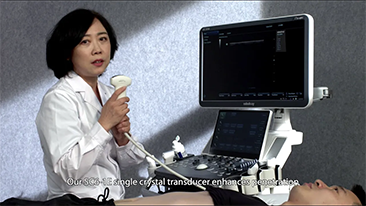

Solusi Pencitraan Umum Resona dari Mindray membantu para dokter mewujudkan diagnosis dan hasil pengobatan yang lebih akurat dan efisien melalui pemerik aplikasi subdivisi yang komprehensif dan alat bantu aplikasi klinis yang efisien.